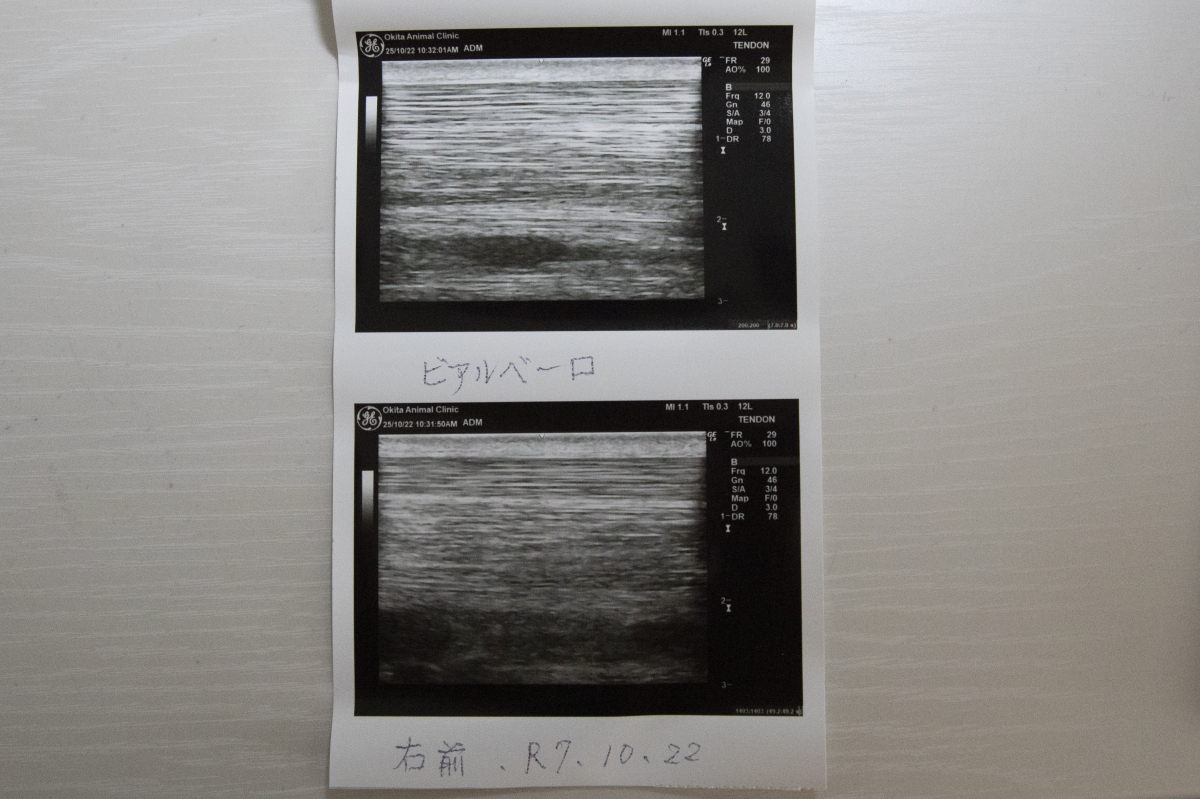

1200mではややスピード不足の印象でしたが、距離を延ばした前走は前半から行きっぷりが良すぎたほどで、かなり噛んでしまって失速したのもやむを得ません。結果的にブリンカーが効きすぎたようで、外してリズム良く折り合えれば結果は違っていたでしょう。現状は脚元にも配慮しながらの調整ですので、固まって攻め込めるようになれば変わってくるはずです。エコー検査のため、10/22に両前脚の毛を刈っています。(ホッカイドウ競馬・桧森邦夫調教師)

※右前屈腱部に慢性的な腫れが見られ、中央退厩時と前走後にエコー検査を受けましたが、腱周囲の腫れが見られたものの、腱自体の炎症は見られないとの診断でした。